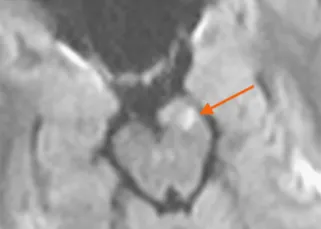

Clinical Studies Guerbet Clinical Studies Clinical Case Studies as seen in Applied Radiology Neurological and Orbital Involvement of Systemic IgG4-related Sclerosing Disease DOWNLOAD Atypical Teratoid Rhabdoid Tumor of the Oculomotor Nerve DOWNLOAD Pediatric Pineoblastoma DOWNLOAD